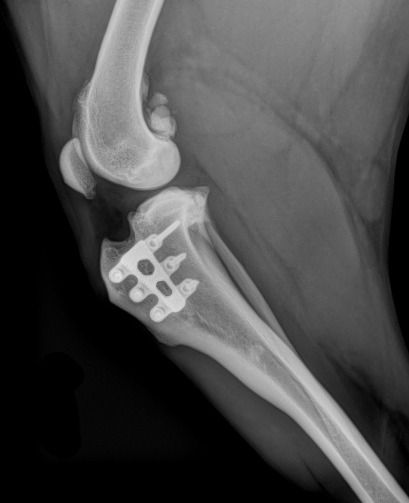

ניתוח זה מבוסס על מחקר ביומכאני שגילה שהכוח שגורם לפריקה (הcranial tibial trust) מתבטל כאשר המישור המפרקי של עצם הטיביה (tibial plateau) ניצב לגיד של הפיקה (patellar tendon). בניתוחי RTTA מבוצע חיתוך עצם (אוסטאוטומיה) של עצם הטיביה לאורך הtibial tuberosity . באתר אנטומי זה גיד הפיקה מתחבר. החלק המנוסר של העצם נדחף קדימה ומקובע במצב הזה ע"י כלוב עשוי טיטניום המחובר עם ברגים לעצם. הניתוח גורם לכך שבמהלך נשיאת המשקל גיד הפיקה ניצב למישור המפרקי של הטיביה והכוח שגורם לפריקה (cranial tibial trust) אינו פועל. באופן ציורי ניתן לומר שניתוח זה אינו משחזר את הרצועה הקרועה אלא מבטל את הצורך בה.

לאחר בדיקה אורתופדית ראשונית של בעל החיים, מבוצעים צילומי רנטגן של הגפה על מנת להעריך את גודל המפרקית (tibial plateau). על גבי צילומי הרנטגן מבוצע תכנון של הניתוח הלכה למעשה. הרדמה לצורך ביצוע הניתוח כוללת הרדמה מקומית לכל הגפה המנותחת המבוצעת ע"י רופא מרדים. בניתוח עצמו מפרק הברך נבחן וקרעים במניסקוס מטופלים (במידה וקיימים). מבצעים חיתוך של עצם הטיביה (על פי התכנון שבוצע בצילומי הרנטגן) לאורך ה הtibial tuberosity, הסטה וקיבוע שלו ע"י כלוב הטיטניום והברגים.

לאחר סיום הניתוח מבצעים צילומי רנטגן חוזרים על מנת להעריך שוב את מידת התזוזה שבוצעה ואת מיקומם של השתלים. ברוב המקרים הכלבים המנותחים משתחררים לביתם ביום הניתוח או ביום שלאחר הניתוח.